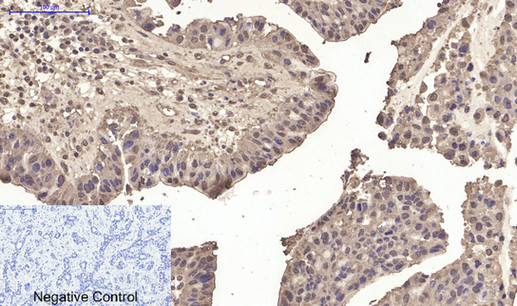

Immunohistochemical analysis of paraffin-embedded Human-liver-cancer tissue. 1,p53 (Di Methyl Lys370) Polyclonal Antibody was diluted at 1:200(4°C,overnight). 2, Sodium citrate pH 6.0 was used for antibody retrieval(>98°C,20min). 3,Secondary antibody was diluted at 1:200(room tempeRature, 30min). Negative control was used by secondary antibody only.